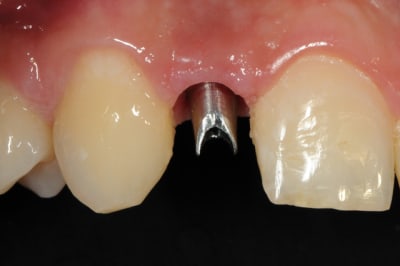

01/09/2010 à 16h28

-cicatrisation de la première vis de cica,

-diamètre plus gros pour la vis de cica

- pilier pour la provisoire

- provisoire moule ION

- ajustage

- polissage soigneux

la suite tout à l'heure, ça sonne à la porte...